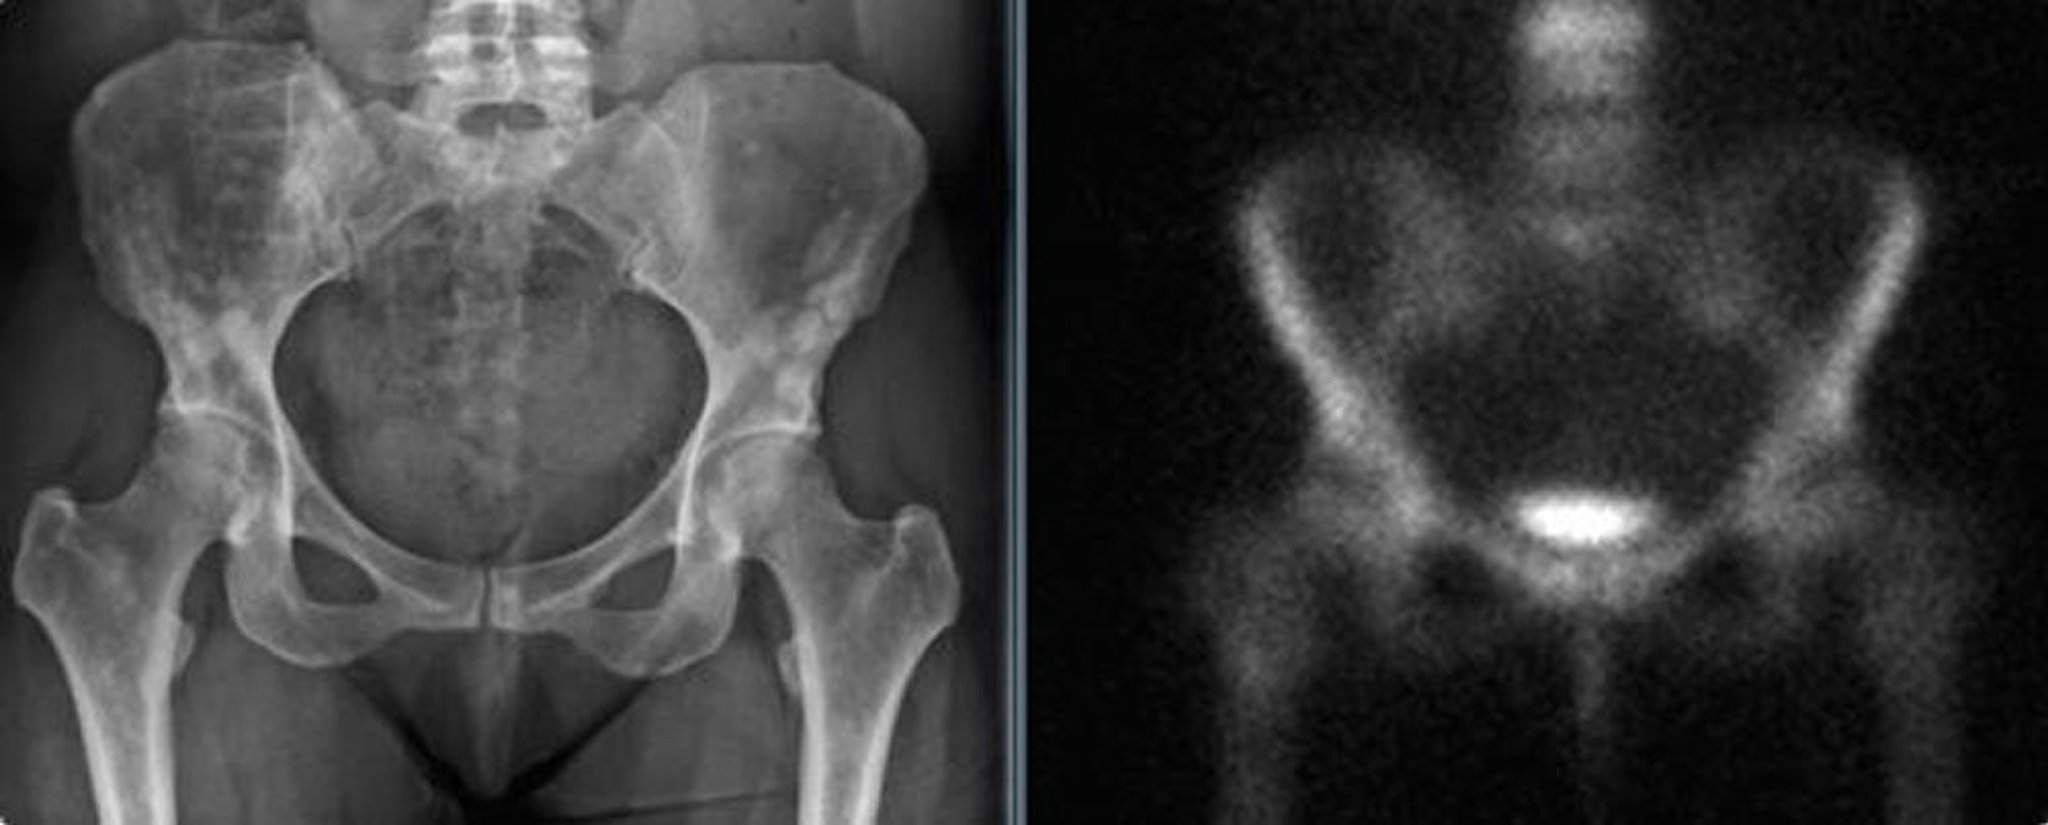

Osteopoiquilose da pelve

A radiografia da pelve (esquerda) mostra osteopoiquilose da pelve em uma mulher adulta. Essas densidades podem ser confundidas com metástases blásticas. A cintilografia óssea (à direita) não mostra captação aumentada significativa.

Imagens cortesia de Michael J. Joyce, MD, and David M. Joyce, MD.